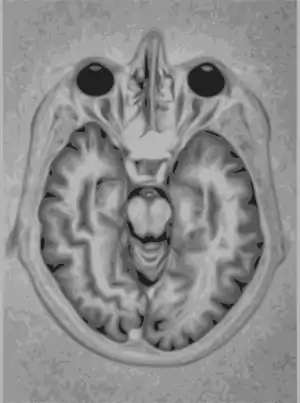

ام آر آی

با استفاده از پویشگر ام. آر. آی امکان عکس گرفتن از تقریباً همه بافتهای بدن وجود دارد. بافتی که کمترین اتمهای هیدروژن را دارد (مثل استخوانها) در تصویر تیره میشود، در حالی که بافتهای دارای اتمهای هیدروژن زیاد (مانند بافت چربی) روشنتر دیده میشوند. با تغییر زمان پالسهای امواج رادیویی امکان کسب اطلاعاتی دربارهٔ بافتهای مختلف موجود وجود دارد.

همچنین یک اسکن ام. آر. آی قادر است تصاویر واضحی را از بخشهایی از بدن که به وسیله بافت استخوانی احاطه شدهاند فراهم سازد بنابراین تکنیک فوق برای بررسی مغز و طناب نخاعی نیز مفید است. به دلیل آن که اسکن ام. آر. آی تصاویر بسیار مشروح و مفصلی را ارائه میدهد، بهترین تکنیک برای یافتن تومورها (اعم از خوش خیم و بدخیم) در مغز میباشد. در صورت وجود تومور از اسکن برای تشخیص گسترش احتمالی آن به بافتهای اطراف مغز استفاده میشود.

این تکنیک به ما امکان میدهد جزییات دیگر در مغز را نیز بررسی کنیم. برای مثال مشاهده رشتههای بافت غیرنرمال که در صورت ابتلا بهام. اس روی میدهد را ممکن میسازد و نیز تغییرات رخ داده در هنگام خونریزی مغزی را نشان میدهد. همچنین تشخیص این که آیا بافت مغز پس از سکته مغزی دچار کمبود اکسیژن شدهاست را میسر میسازد. اسکن ام. آر. آی قادر به نشان دادن قلب و عروق خونی بزرگ در بافت اطراف آن است لذا تشخیص نواقص مادرزادی قلب و تغییرات در ضخامت عضلات اطراف آن پس از یک حمله قلبی را ممکن میسازد. تفاوت ام. آر. آی و سی تی اسکن در این است که با ام. آر. آی تصویربرداری از تقریباً هر زاویهای امکان دارد، در حالی که سی تی بهطور افقی عکس میگیرد. هیچ اشعه یونیزان (اشعه ایکس) در ایجاد تصویر ام. آر. آی دخالت ندارد. اسکنهای ام. آر. آی بهطور کلی مفصل تر و مشروح تر هستند. تفاوت بین بافت نرمال و غیرنرمال در اسکن ام. آر. آی نسبت به سی تی اسکن واضح تر است.